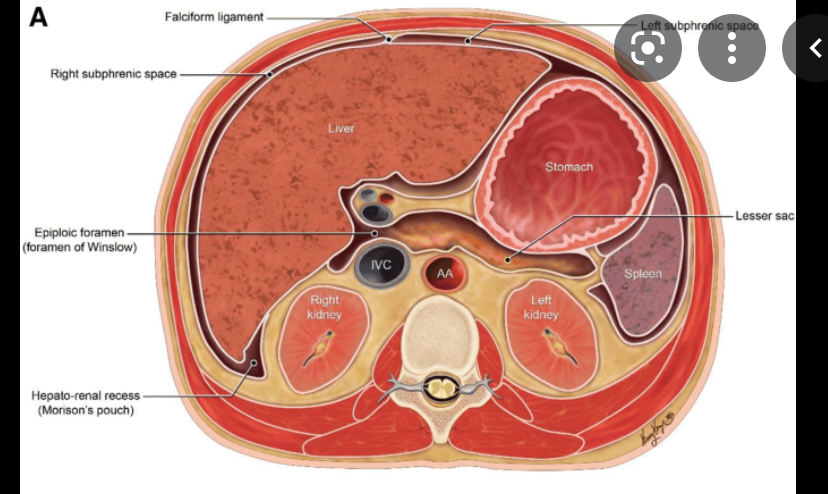

Complications of cholecystectomy

what is this called?

- 0.5-5%

- biliary obstrction

- clipping or thermal injury to CBD

- Postoperative fibrosis

- usually requires percutaneous drainage

- Biliary leak causing peritonitis and/or biloma

- CD stump leak,

- injury to CBD,

- leak from small luschka bile ducts draining directly in GB

- Detection of bile leaks

- HIDA scan

- ERCP

- Transhepatic cholangiogram

- MR with heaptobiliary contrast

- Other

- retained stones

- stones dropped in peritoneal cavity (Morison Pouch)

- Bowel perforation

- Hemorrhage

- infection

- The bile ducts of Luschka, or subvesical ducts, are small ducts which originate from the right hepatic lobe, course along the gallbladder fossa, and usually drain in the extrahepatic bile ducts. Injuries to these ducts are the second most frequent cause of postcholecystectomy bile leaks